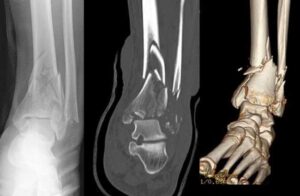

Imaging studies play a vital role in diagnosing pilon fractures and planning treatment, particularly if surgery is required.- X-rays: These provide detailed images of the bones and are used to identify fractures or joint misalignments in the leg, ankle, and foot.

- Computed Tomography (CT) Scans: CT scans offer more precise information about the fracture's complexity, showing detailed fracture lines and aiding in surgical planning. A CT scan may be performed immediately or after the application of an external fixator, depending on the treatment timeline.

To fully evaluate your fracture, your doctor may recommend an x-ray (left), a CT scan (center), or a three-dimensional CT scan (right).